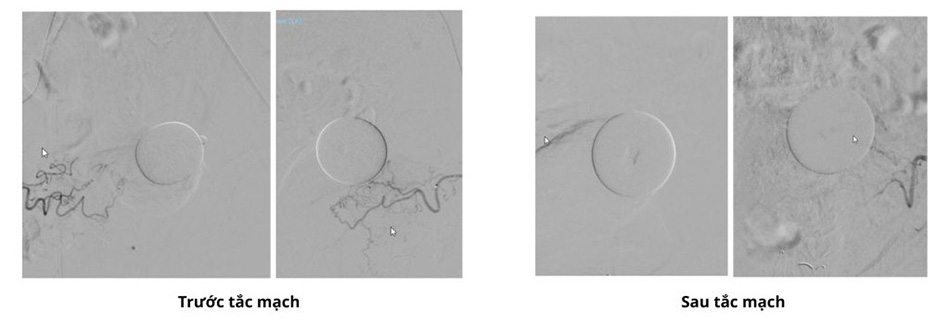

Hình ảnh DSA trước và sau thủ thuật nút mạch. Động mạch tiền liệt tuyến đã được thuyên tắc hoàn toàn

Được người quen giới thiệu, ông đến bệnh viện FV để thăm khám. Bác sĩ BS.CKI Huỳnh Hữu Danh, khoa Chẩn đoán hình ảnh và Can thiệp Điện quang cho biết ông H. có khối tăng sinh tiền liệt tuyến rất lớn, chèn ép bàng quang. Bác sĩ Danh đề nghị điều trị cho bệnh nhân bằng phương pháp thuyên tắc mạch. Đây là thủ thuật dùng một ống thông siêu nhỏ luồn vào động mạch đùi đi tới mạch máu nuôi tuyến tiền liệt, sau đó bơm chất gây tắc để ngắt nguồn dưỡng chất nuôi tiền liệt tuyến. Theo thời gian, khối u bị “bỏ đói” sẽ teo nhỏ lại, không gây chèn ép bàng quang và niệu đạo, và các vấn đề bí tiểu, tiểu rắt, tiểu nhiều lần sẽ dần được cải thiện. Ông H. đồng ý với phương án điều trị này.